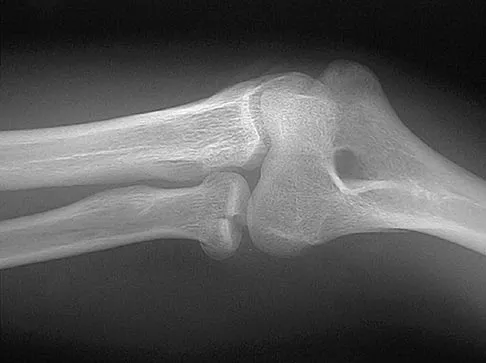

Figure 43 shows the lateral radiograph of a 12-year-old boy with mild osteogenesis imperfecta who injured his left elbow after pushing his brother. Treatment should consist of

Explanation

The patient has a displaced fracture of the apophysis of the olecranon for which most authorities recommend surgical treatment. In older children, stability of the reduction may be achieved by the use of two parallel medullary Kirschner wires and a figure-of-8 tension band loop of either stainless steel wire or absorbable suture. The use of an absorbable suture does not require removal of the implant. Absorbable suture alone is best used in very young patients who have this type of injury. An intramedullary screw would pose an unnecessary risk of future growth disturbance. A displaced, isolated fracture of the apophysis of the olecranon is an unusual injury in a child. It has been suggested by several authors that children who have osteogenesis imperfecta may be especially prone to this injury. One study reported seven of these fractures occurring in five children who had the mild form of osteogenesis imperfecta (Sillence type IA). The authors of this study suggest that the diagnosis of osteogenesis imperfecta be considered in any child who has a displaced fracture of the apophysis of the olecranon, especially when the injury is associated with relatively minor trauma. Stott NS, Zionts LE: Displaced fractures of the apophysis of the olecranon in children who have osteogenesis imperfecta. J Bone Joint Surg Am 1993;75:1026-1033. Gaddy BC, Strecker WB, Schoenecker PL: Surgical treatment of displaced olecranon fractures in children. J Pediatr Orthop 1997;17:321-324.